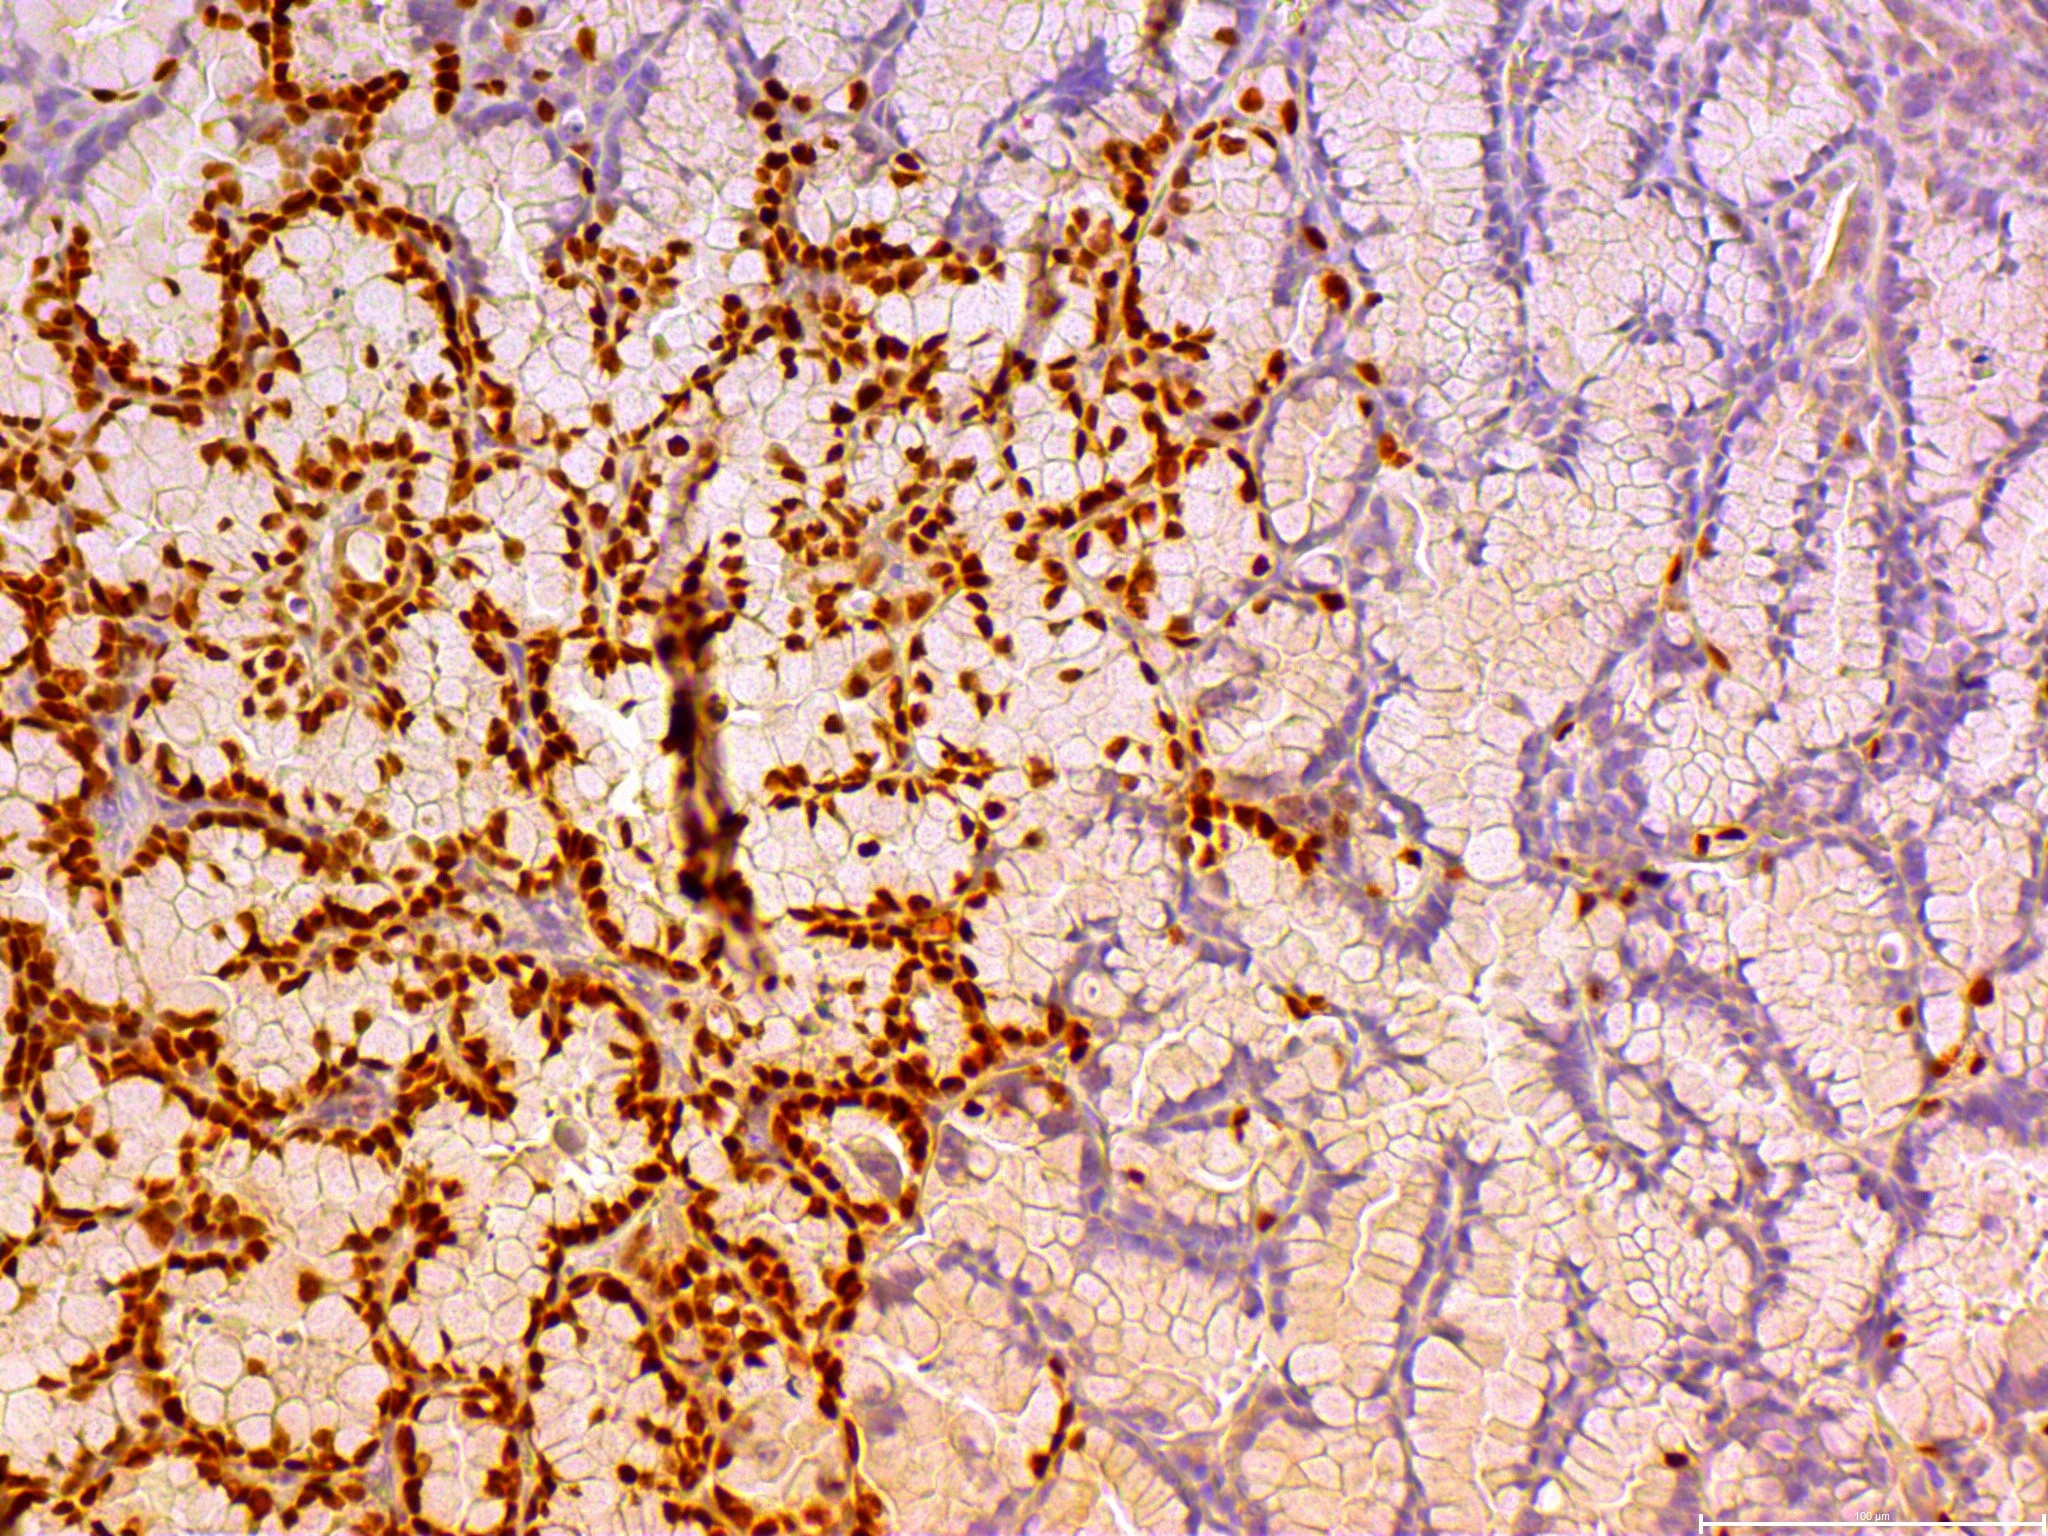

Cell state transitions underlie cancer progression and the response to chemo- or molecularly-targeted therapy. As cancer cells evolve toward their most aggressive forms, their cellular differentiation status generally degrades, becoming more developmentally primitive. We have uncovered multiple roles for specific tumors suppressor genes that unlock cell state plasticity when inactivated. Understanding the molecular constraints on cell state transitions has the potential to identify strategies that can limit cell state transition as a mechanism of resistance and increase the durability of targeted therapies.

In this space, we use novel genetically engineered animal and tumor spheroid models to identify relevant cell state transitions and link these changes with alterations in the genetic and epigenetic landscape. Contact David to learn more about joining this team.